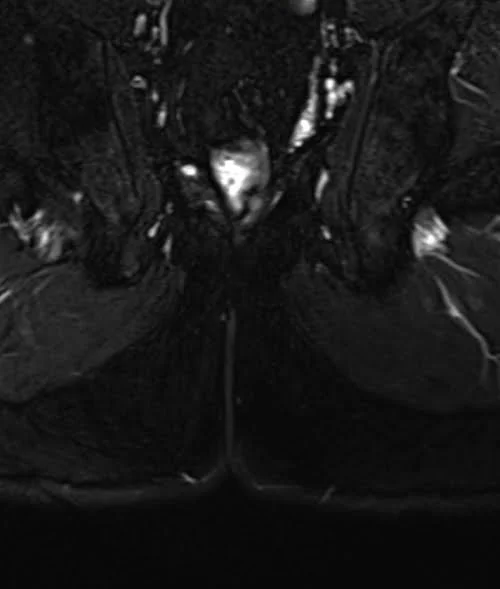

LUMBOSACRAL PLEXUS